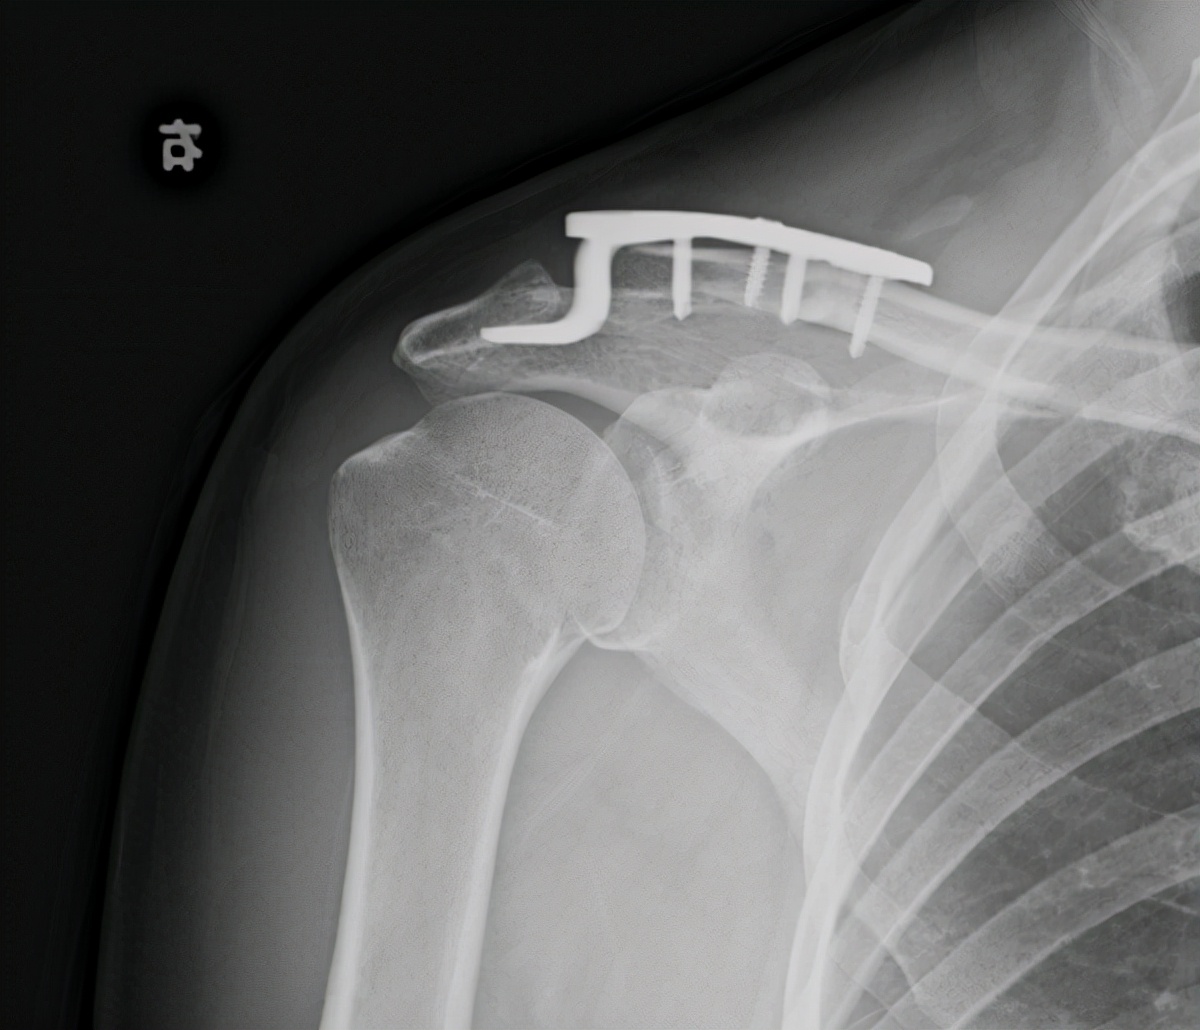

肩锁关节脱位术前术后

肩锁关节脱位锁骨远端骨折关节镜下微型钢板固定喙锁 斜方韧带重建术

右肩锁关节脱位纽扣钢板固定